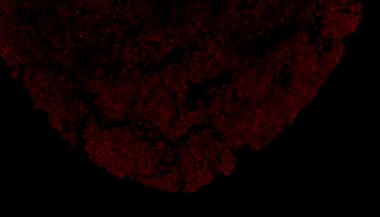

Absin多重荧光免疫组化服务

四色多重荧光免疫组化染色试剂盒(鼠兔通用二抗)